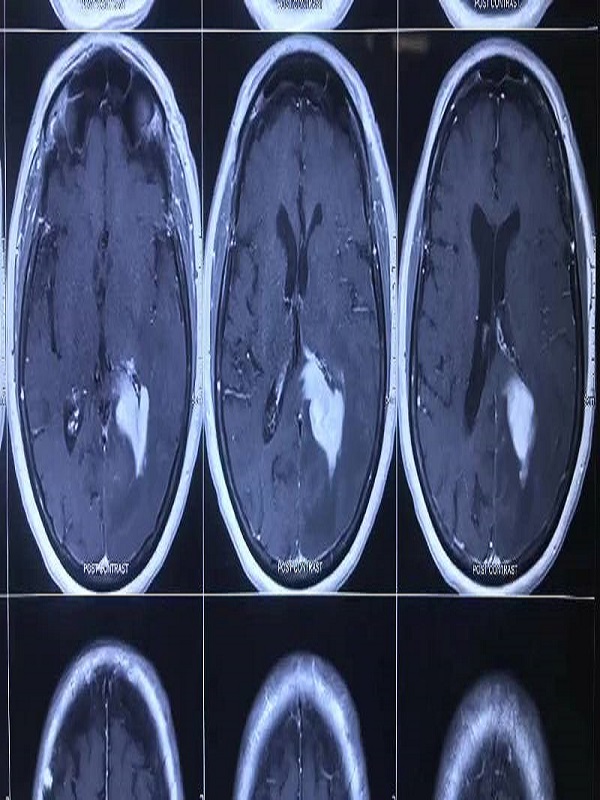

Brain Tumor

A brain tumor is a mass or growth of abnormal cells in your brain. Many different types of brain tumors exist. Some brain tumors are noncancerous (benign), and some brain tumors are cancerous (malignant).